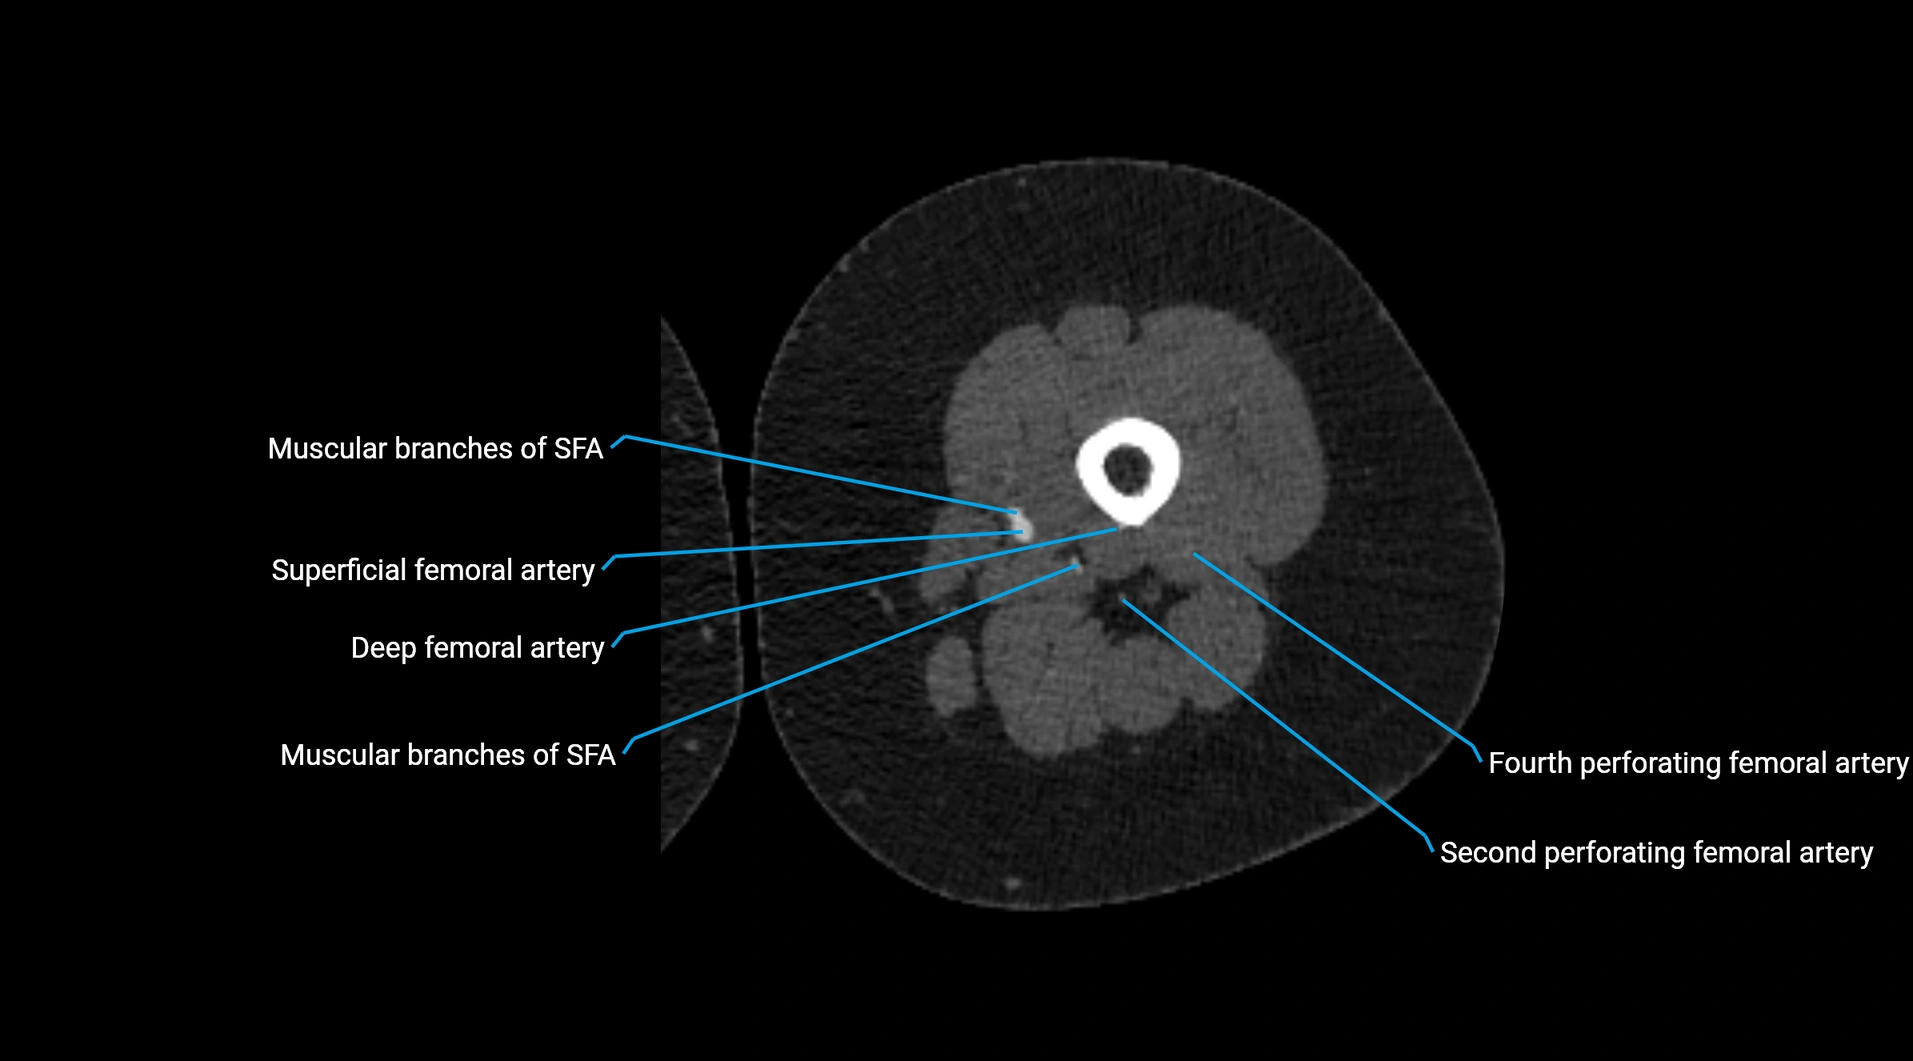

CT images

image